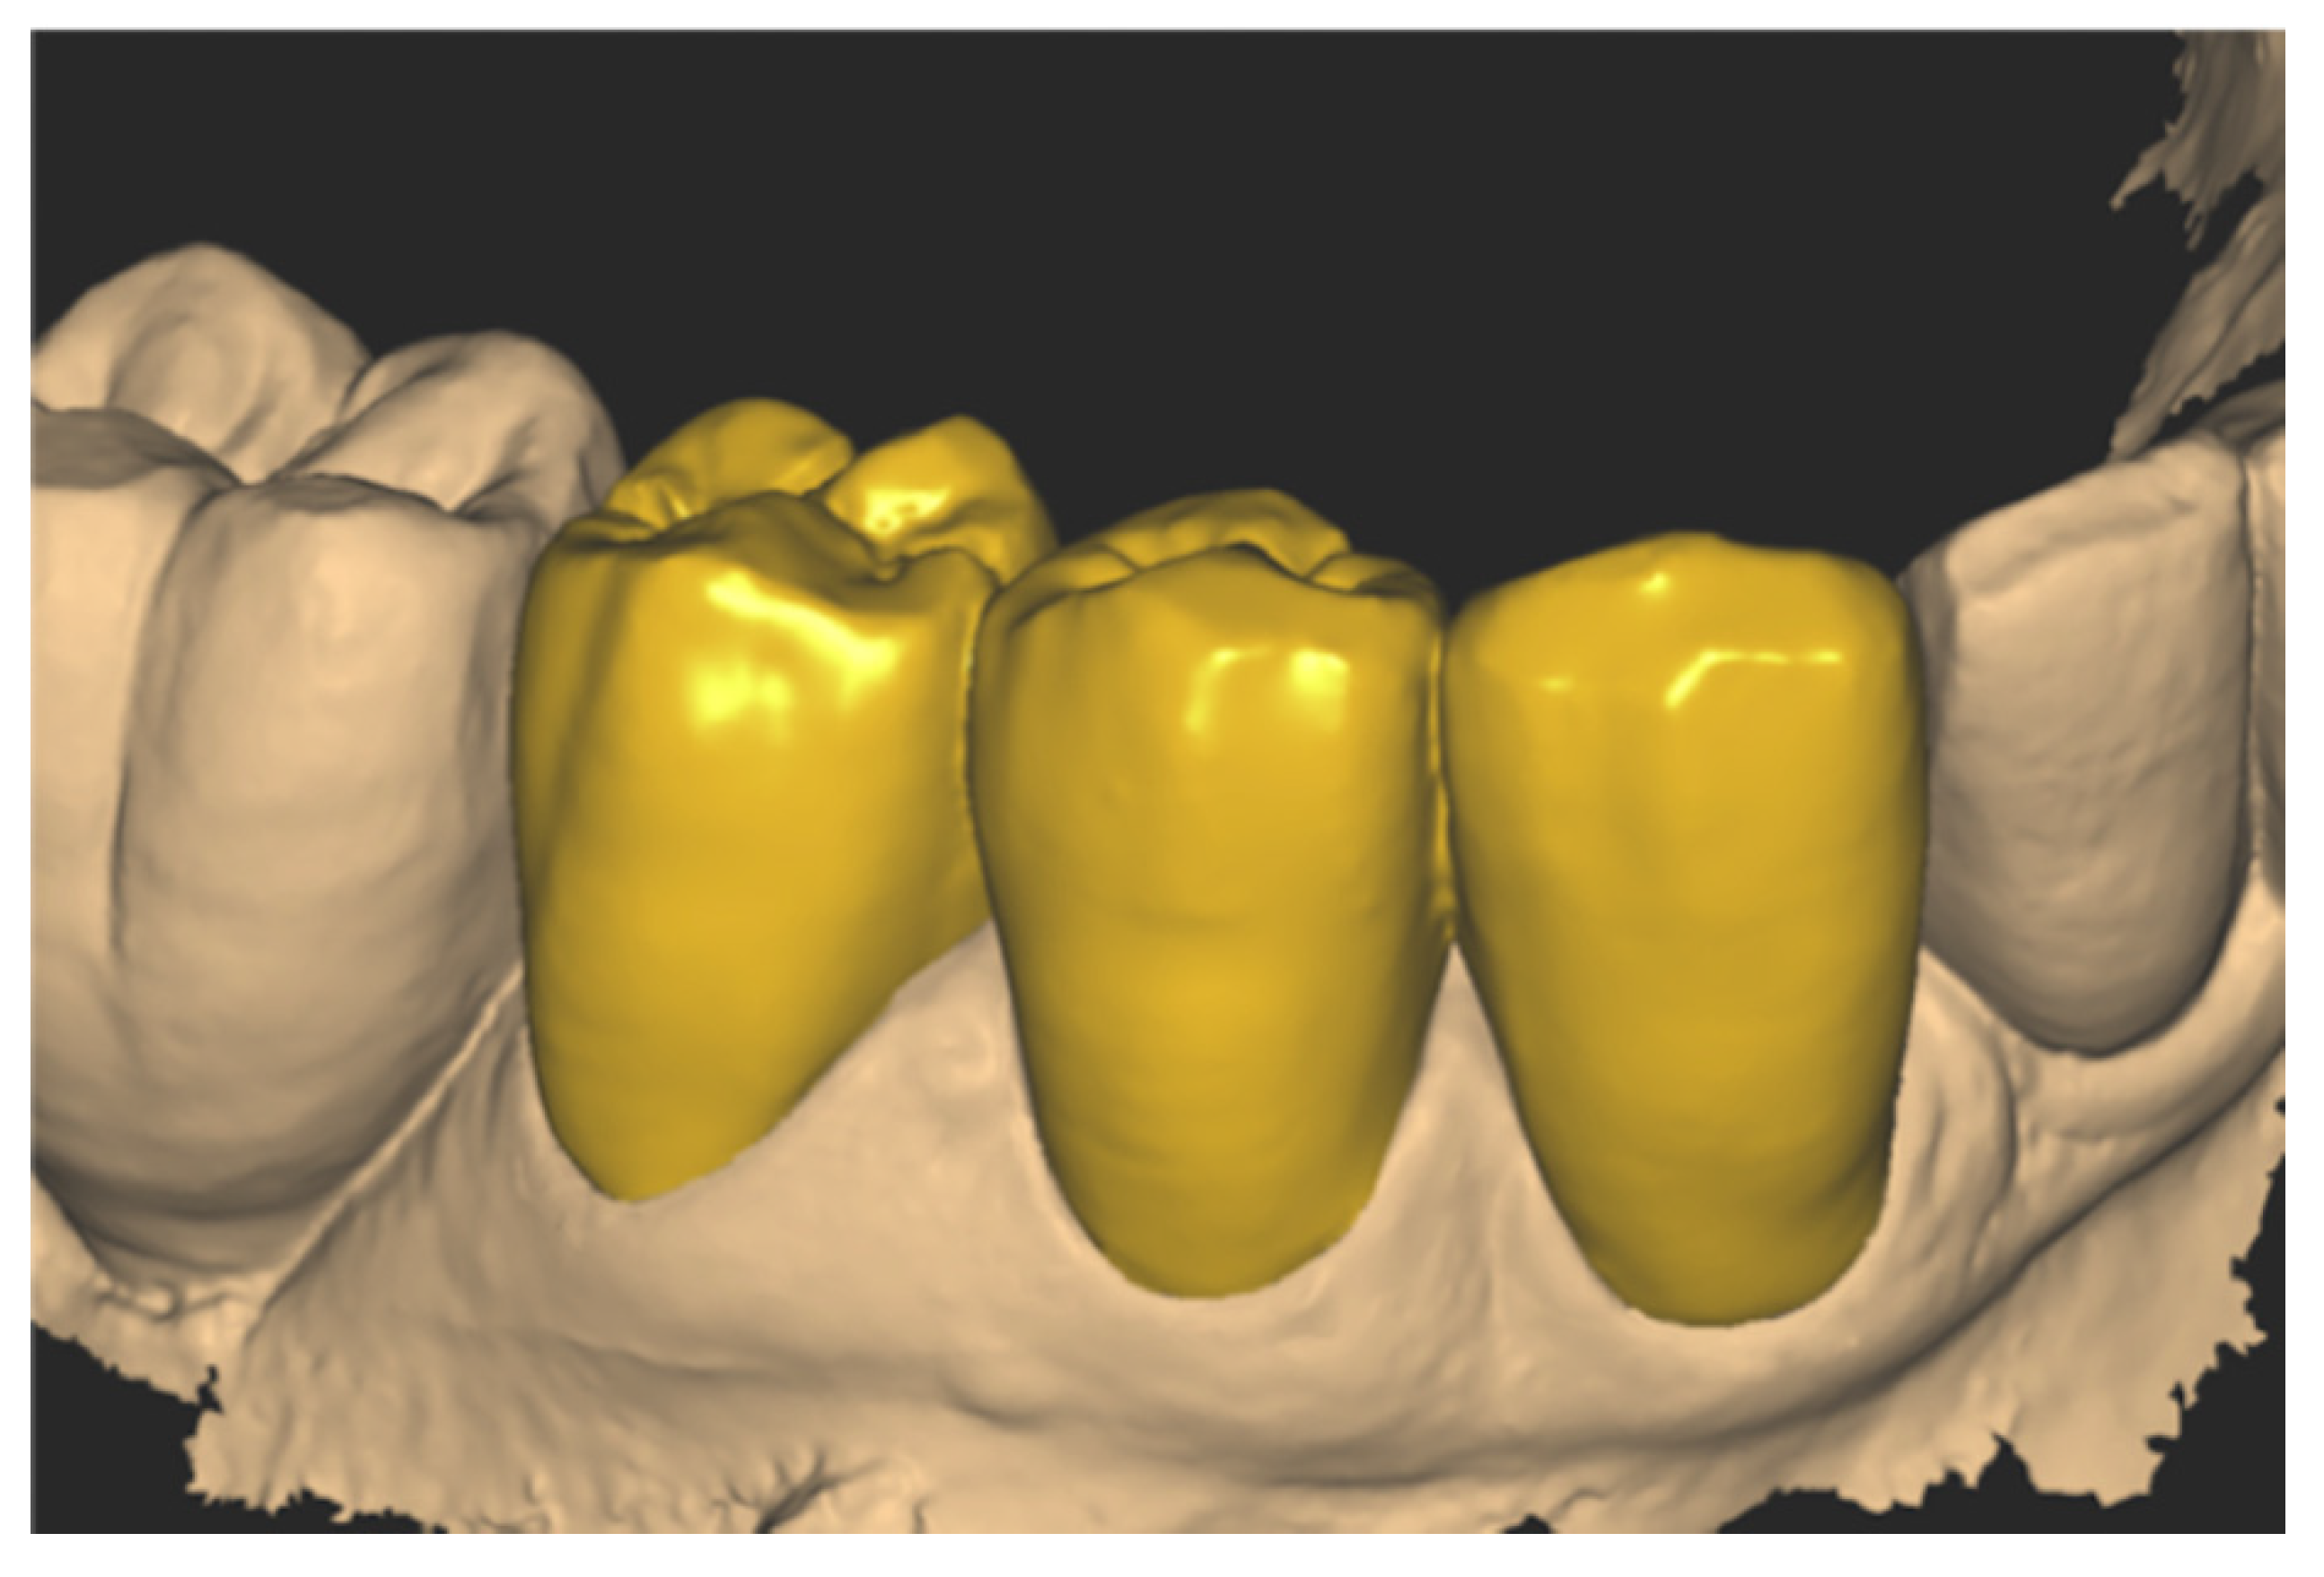

Figure 16.

Modelling the zirconia crowns.

To further detail the workflow and to serve as a proof-of-concept clinical case, crowns were designed and milled from 1200 MPa zirconia blocks (Dental Direkt, Spenge, Germany). To test ex vivo the fitting of the zirconia crowns, a master model was printed using a Form 2 printer (Formlabs, Somerville, MA, USA), and the resin “Model” with accuracy on the z-axis set to 25 µm.